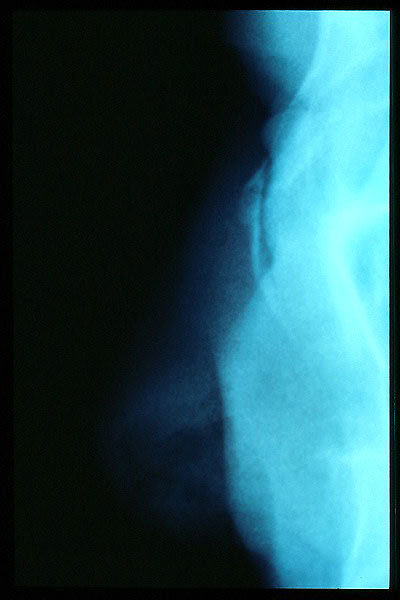

Hernia de hiato por deslizamiento al TGED.

Hernia de hiato por deslizamiento al TEGD.